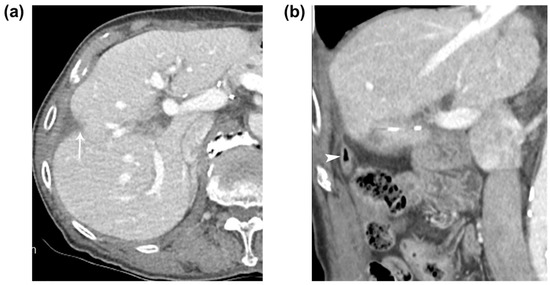

An immediate post-RFA contrast-enhanced CT scan demonstrated a low-attenuating ablated area that covered the tumor and the air-filled appendix, which extended superiorly from the cecum to the perihepatic space near the ablated zone of segment 5 of the liver, with a thickened appendiceal tip (Figure 2a). The patient was closely monitored and treated with intravenous antibiotics. On the fifth day after RFA, the patient’s laboratory results showed elevated aspartate aminotransferase and alanine aminotransferase levels, as well as an elevated high-sensitive C-reactive protein level. The patient presented with intermittent right upper abdominal pain and chills after the RFA, and a follow-up CT scan performed 7 days later revealed the formation of an abscess in the ablated zone and adjacent perihepatic space, although communication between the appendix and the ablated zone was not clear on the CT scan. A 10-French pigtail percutaneous drainage catheter was inserted into the hepatic abscess between the ablated zone and the perihepatic appendix (Figure 2b), and fluoroscopic imaging showed a fistulous tract between the ablated zone and appendix (Figure 2c). Abscess formation after percutaneous ultrasound-guided radiofrequency ablation for a 1.2 cm subcapsular hepatocellular carcinoma in segment 5 of the liver. (a) Immediate follow-up contrast-enhanced coronal CT image after ultrasound-guided radiofrequency ablation depicts a low-attenuating ablated area (arrows) which sufficiently covers the tumor (asterisk) and an air-filled perihepatic appendix (arrowheads) with a thickened tip from cecum (C). Note the small air density (curved arrow) between the ablated area and the appendiceal tip. (b) Follow-up contrast-enhanced coronal CT image taken 7 days after the RFA depicts abscess formation in the ablated zone and adjacent perihepatic space (arrow) and a thickened perihepatic appendix (arrowheads). (c) A 10-French pigtail percutaneous drainage catheter (arrow) was inserted into the sinus between the ablated area and the appendiceal tip. The fluoroscopic image depicts the contrast-filled appendix (arrowheads) with mottled air density and cecum (C). After 1 month, the patient’s clinical symptoms and laboratory findings subsided and improved, and a follow-up tubogram showed an improving abscess with a remaining fistula. Surgical treatment was initially considered, and the potential difficulties due to postoperative adhesion and potential postoperative complications were explained to the patient. However, the patient opted against this approach, leading us to decide on a conservative treatment. The patient was discharged following the removal of the percutaneous drainage catheter.